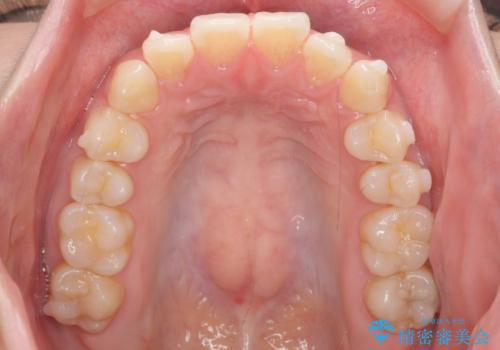

- 前歯のがたつきをきにされていました。

上下の前歯をやすりがけする処置(IPR)を行い、前歯の並びを出っ歯にしないようにしながら整えました。